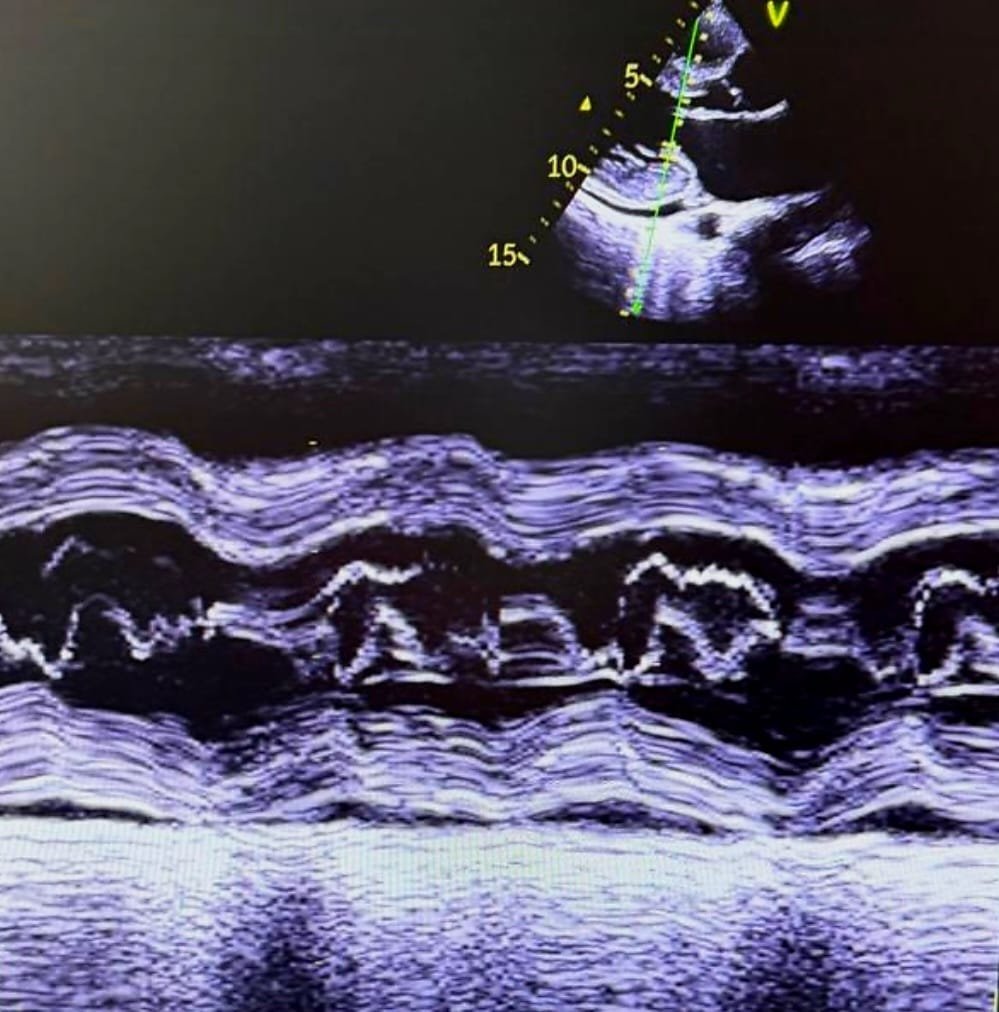

Echocardiographic Findings

Images and videos:

| Echocardiography revealed: |

| Features consistent with hypertrophic cardiomyopathy |

| Systolic anterior motion (SAM) of the posterior mitral leaflet (PML) |

| Dynamic LVOT obstruction |

| LVOT mean pressure gradient: |

| 14 mmHg at rest |

| 20 mmHg on Valsalva |

| Mild subaortic obstruction |

Notably, SAM involved the posterior mitral leaflet — an uncommon variant — rather than the classical anterior leaflet SAM seen in obstructive HCM.

- Classic hypertrophic cardiomyopathy–related obstruction is mediated by SAM of the anterior mitral leaflet, where Venturi forces and drag pull the leaflet into the septum during systole. Posterior leaflet involvement indicates altered mitral apparatus geometry, suggesting:

- Posterior leaflet SAM is rare and often under-recognized. It may produce dynamic LVOT obstruction even when septal hypertrophy is not extreme. The modest gradient in this patient suggests early or compensated obstruction, which may become hemodynamically significant under stress, dehydration, tachycardia, or reduced preload.